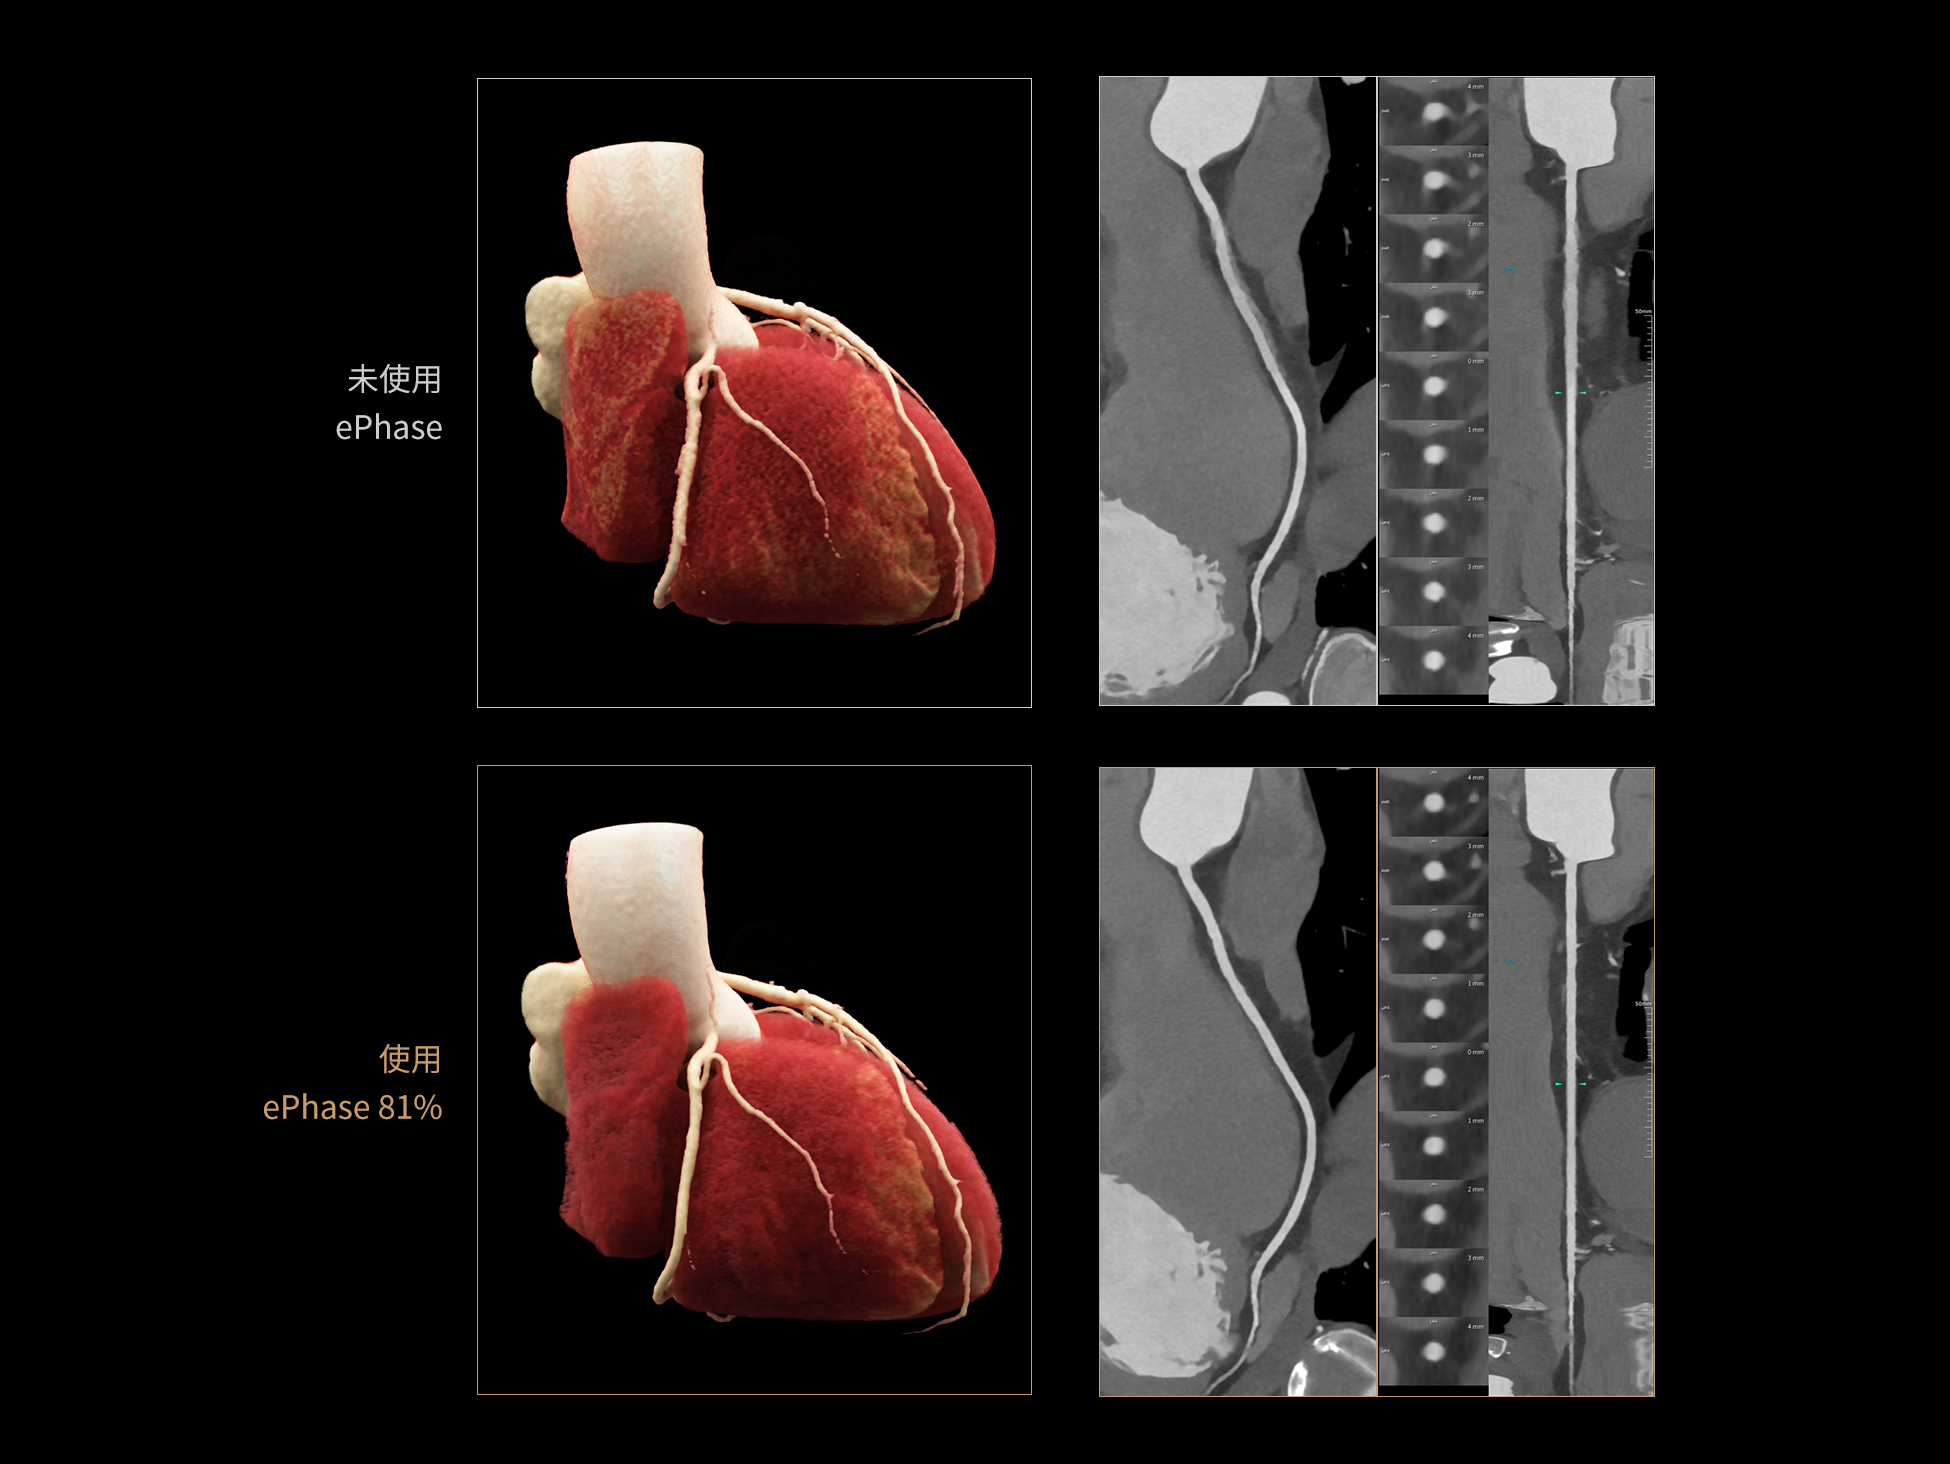

CardioBoost:专属网络设计,重塑心脏影像表现

相同辐射剂量下

低对比度分辨率提升

相同辐射剂量下

空间分辨率提升

相同低对比度分辨率下

辐射剂量减少

相同辐射剂量条件下

图像噪声减少